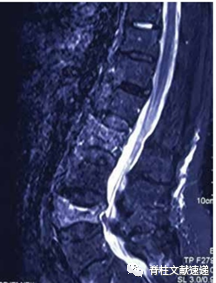

图注:没有伴随筋膜损伤的椎体压缩性骨折在T1 WI(A1)、T2 WI(A2)和T2-STIR WI(A3)MRI图像上无明显信号变化。伴有筋膜损伤的椎体压缩性骨折在 T1 WI (B1) 显示低信号,在 T2 WI (B2) 和 T2-STIR WI (B3) 显示高信号。